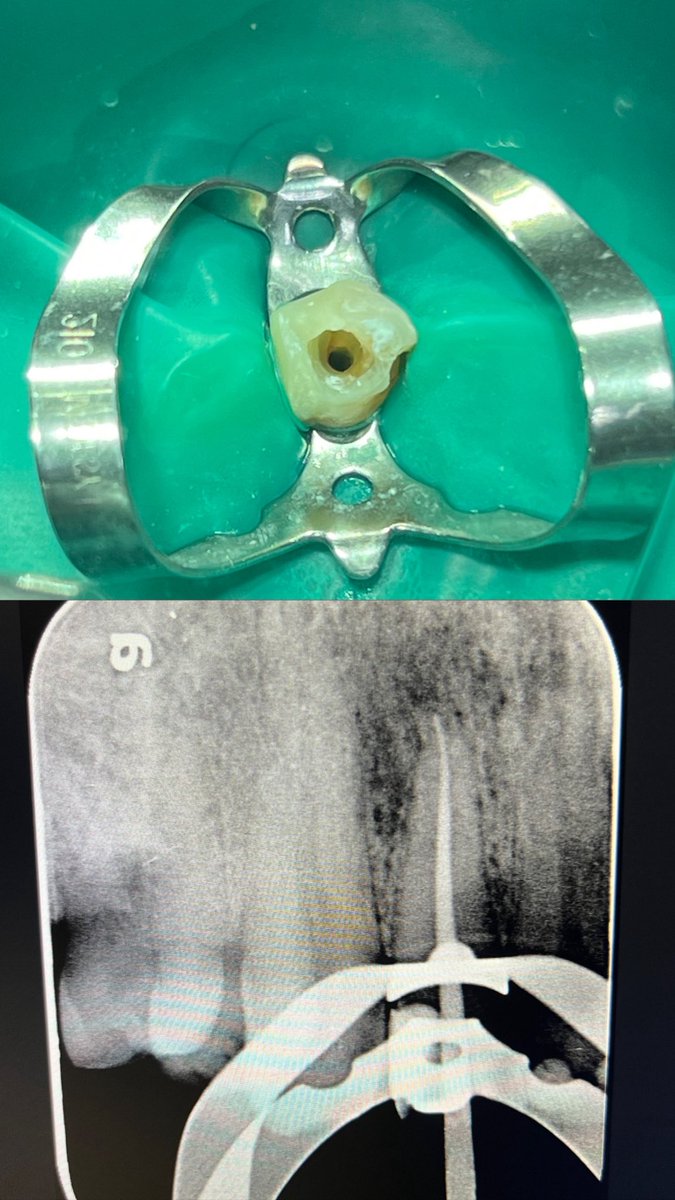

حالة جديدة اليوم ❤️

Root Canal Treatment for #36

The patient complained of severe pain,after examination we decided to do RCT.

Dx: SIP,NAP

ML wall is replaced then started RCT.

Single Cone and BC Sealer are used

✅✅

#endodontics